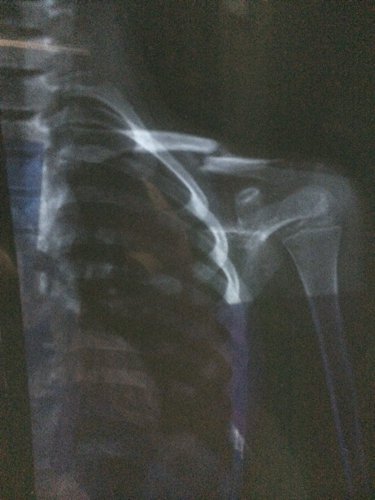

小孩八岁半,在2月27日那天因足球训练导致锁骨骨折,当时采用医生建议的保守治疗,可现在一个多月了照片发现基本没长,照这样下去还能长好吗?该怎么办?是否要手术治疗?

病情分析: 应及时手术,术后并采取固定措施以利恢复。 指导意见: 术后可以多食瘦肉、鱼、鸡蛋、牛奶、豆类食品以及新鲜蔬菜、水果等,注意逐渐恢复锻炼。